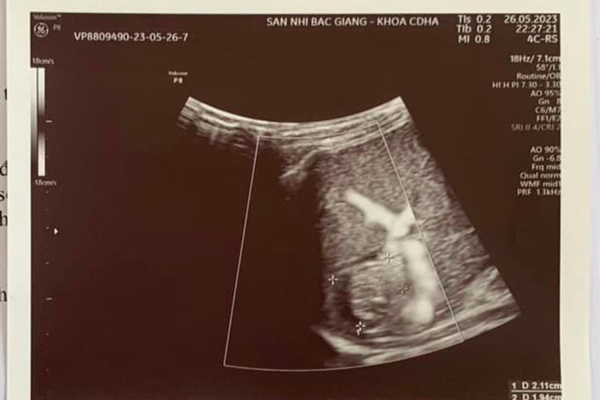

Kết quả siêu âm ổ bụng phát hiện có nhiều dịch tự do ổ bụng và hình ảnh đường vỡ lách khá rõ. Với chẩn đoán trẻ bị vỡ lách trong chấn thương bụng kín, các bác sĩ Khoa Ngoại đã chỉ định làm các xét nghiệm cấp cứu, chuyển bệnh nhi lên phòng phẫu thuật và sẵn sàng truyền máu trong khi mổ.

Hình ảnh siêu âm cho thấy lá lách bị vỡ đôi. Ảnh: BVCC

Tiếp đó, bác sĩ kiểm tra lá lách đã bị vỡ thành 2 phần, đường vỡ qua cuống lách không thể bảo tồn được nên đã quyết định cắt lách để cứu sống bệnh nhi. Sau phẫu thuật, huyết động bệnh nhi ổn định, sức khỏe tiến triển tốt. 7 ngày sau, bé được xuất viện.